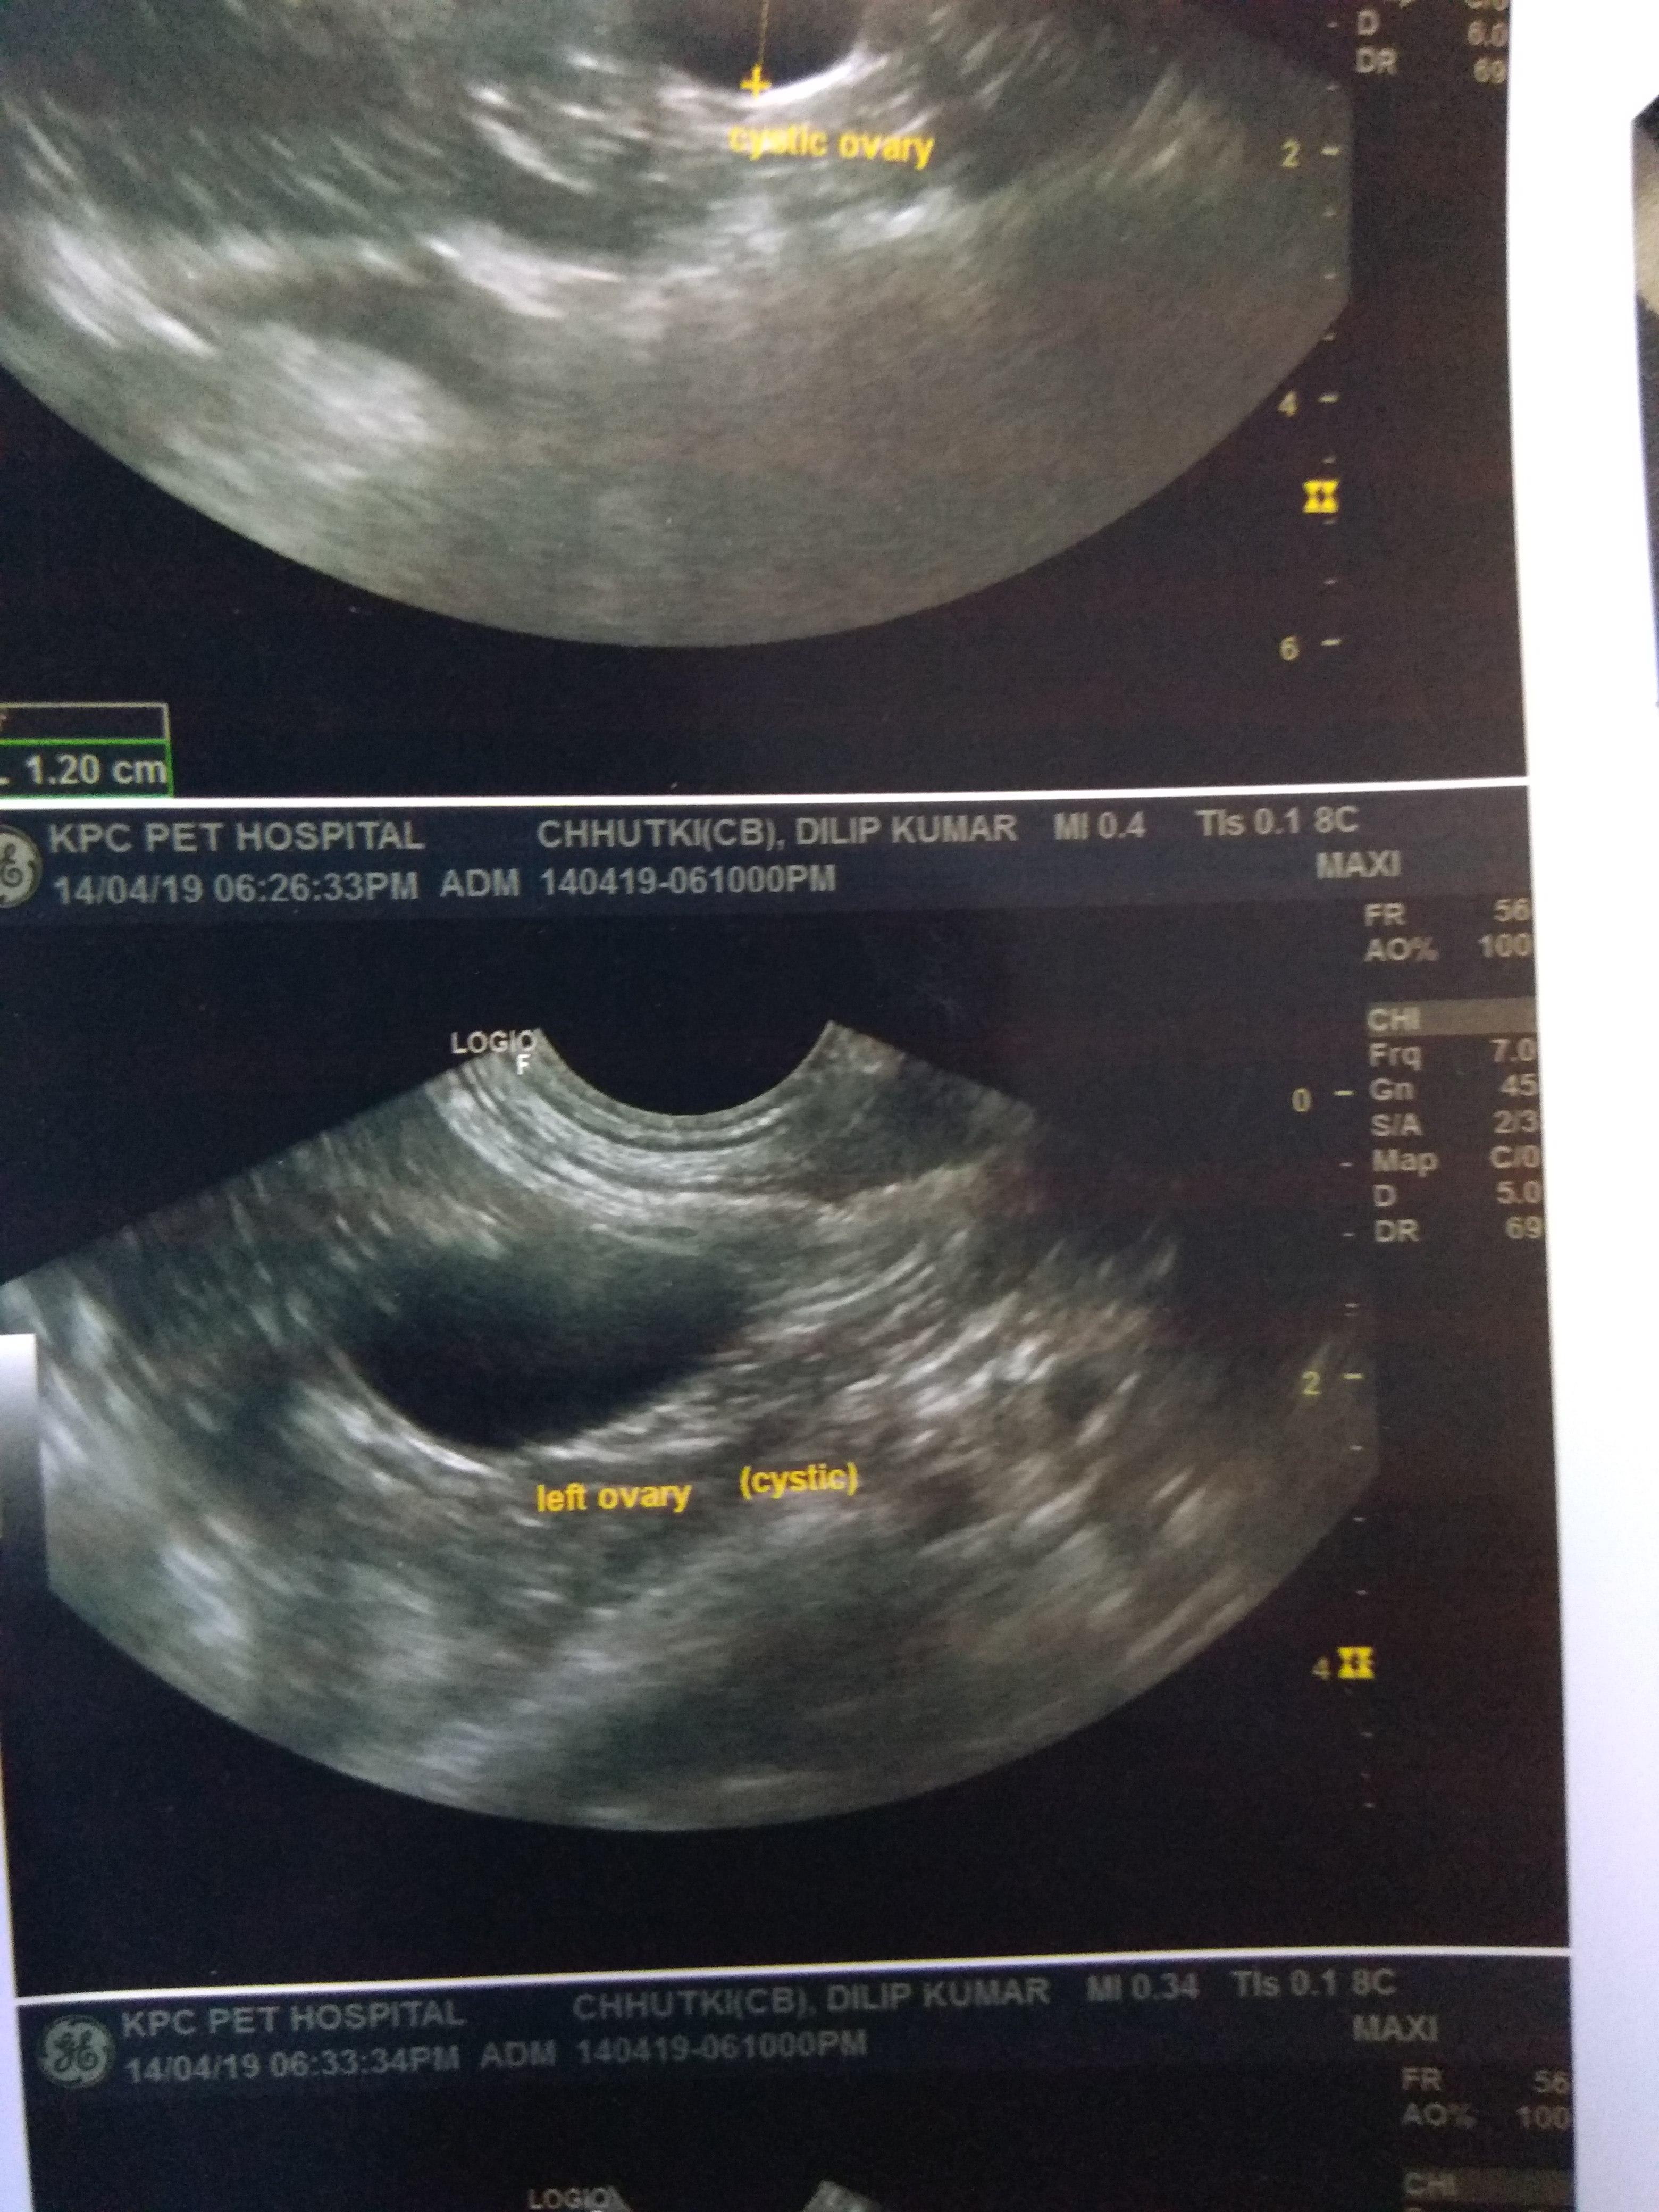

My dog is in heat n last month in USG cystic ovary in left side.she was never vaccinated for distemper.she is 8 yrs old n never dewormed also.she is not a puppy so does she need distemper vaccination?also is deworming needed before vaccination?I don't know if she has heartworms also if it is do then distemper vaccination b fatal?can distemper vaccination cause brain inflammation?vet told it will b a 7 in 1 shot so dangerous?heartworms (not sure)+ heat+cystic ovary+never dewormed+old age+shots?

This question includes photos that may contain sensitive content. Click to view.